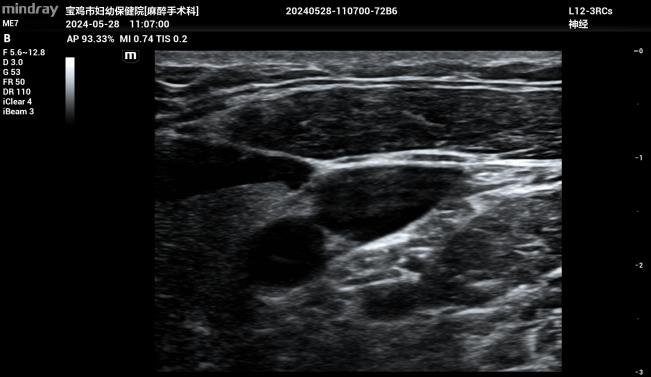

据了解,中心静脉置管术是指:经任何一条静脉插管使尖端达到上腔静脉的穿刺技术,常用穿刺部位为锁骨下静脉、颈内静脉、股静脉。对于病情危重的ICU患者,大多需要中心静脉置管,建立深静脉通道,快速输入所需药物,迅速传达全身各个组织,及时挽救和维持生命。改良式超声引导下中心静脉置管或动脉置管术是:在高频超声探头超声引导下,通过“针尖抖动法”“靶环消失征”判断穿刺进入血管的情况,实时显示血管解剖结构,清晰观察穿刺针在血管内的走向和位置。此技术特别适用于血管细小且位置较深的婴幼儿,可明显提高置管成功率,缩短穿刺时间,提升安全性,减少并发症。

据介绍,该技术是市妇幼保健院麻醉手术科主任张茂鹏在重庆医科大学附属儿童医院学习并引进开展的,目前已开展改良式超声引导下中心静脉导置管和挠动脉穿刺置管术50例。本病例是医院该技术首次应用于2.6公斤新生儿大范围肠切除吻合术,促进了小儿外科手术向更高难度进军。此技术也可应用于产科危重手术,为危重新生儿、婴幼儿、孕产妇手术提供了更为精准和安全的保障措施。